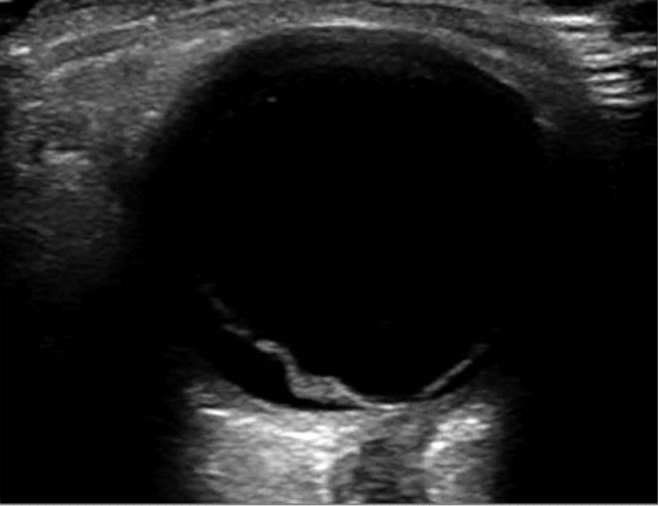

網膜剥離(Retinal Detachment)

Lahham S, Shniter I, Thompson M, et al. Point-of-Care Ultrasonography in the Diagnosis of Retinal Detachment, Vitreous Hemorrhage, and Vitreous Detachment in the Emergency Department. JAMA Netw Open. 2019 Apr 5;2より引用

- 高輝度の膜状構造物として描出される

- 網膜が硝子体腔内で波打つように浮遊する像が特徴的